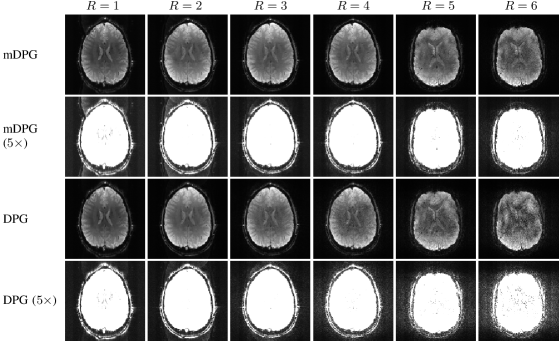

Figure 1 shows ACS data and reconstruction results from the in vivo gradient-echo EPI brain data with an axial slice orientation. The ACS data in this case does not have strong artifacts, although close inspection does reveal that ACS ghost artifacts are present. This can be further appreciated in Supporting Information Fig. S4 where the same images are shown with amplified image intensity to highlight ghost characteristics in the image background. As can be seen, all ghost correction methods work well at smaller acceleration factors, although performance begins to degrade at larger acceleration factors. We observe that, compared to other methods, the visual quality of the MUSSELS reconstruction seems to degrade most rapidly as a function of acceleration factor, which is consistent with previous observations [18]. The mDPG method had qualitatively better performance than MUSSELS in this case. However, a close inspection of the images reveals that the mDPG results are not entirely ghost-free even for the unaccelerated () case. This may be expected due to the artifacts and mismatches that are present in the ACS data. Although mDPG does not attempt to correct the ACS artifacts, it should be noted that the original DPG method does try to correct them through pre-processing. Results showing the qualitative performance of the original DPG method are shown in Supporting Information Fig. S5, where we observe that the ghost artifacts still exist, though as expected, are less prominent than were observed for mDPG. In spite of the ACS artifacts, the AC-LORAKS reconstruction still has good performance at low acceleration factors and does a good job of suppressing ghosts in the background regions of the image at all acceleration factors, although exhibits substantial degradation in image quality at the highest acceleration factors (with artifacts similar to those observed for highly-accelerated parallel imaging reconstructions). However, the RAC-LORAKS reconstruction appears to have much higher quality than the other methods, even at very high acceleration factors like . (Note that when , the effective acceleration factor is when each readout gradient polarity is considered separately. This leads to a highly ill-posed inverse problem).

Figure 1: ACS data and reconstruction results for in vivo gradient-echo EPI brain data with an axial slice orientation for different parallel imaging acceleration factors. Note that the first four acceleration factors (-) were acquired from one subject during a single scan session while the last two acceleration factors () were acquired from a different subject on a different day, which explains the visual discontinuity between these cases.